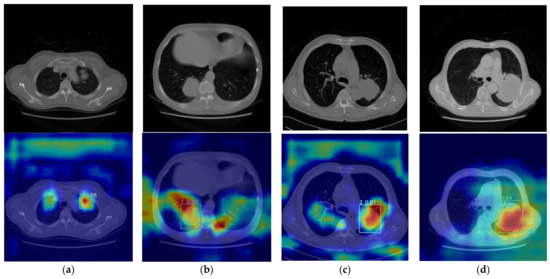

4.5. Experimental Results Visualization